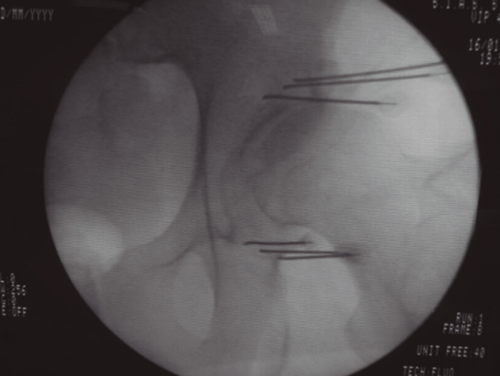

Aunque la articulación de la cadera se afecta con menos frecuencia que la rodilla, también parece despertar menos curiosidad e interés de las publicaciones, pues son muchas menos que sobre la rodilla. La inervación de la cadera está bien estudiada (24,25,26). El resumen de todas estas publicaciones es que la cápsula articular de la cadera recibe inervación en su cara anterior de los nervios femoral (cuadrante supero externo) y obturador en el cuadrante ínfero interno. Se ha demostrado que la denervación de la cápsula articular en la cara anterior produce un alivio del dolor en los pacientes con coxartrosis avanzada que no pueden ser tratados con una prótesis total debido a diferentes factores (edad avanzada, comorbilidades o riesgo quirúrgico elevado). Esquematizando mucho la inervación de la cara anterior de la cadera resumiría en que las ramas articulares del femoral se localizan en la parte superior y externa del cotilo femoral, mientras que las ramas articulares del obturador se localizan en la parte inferior sobre la rama descendente del isquión en su unión con el borde inferior del cotilo. La primera publicación describiendo una técnica de denervación con radiofrecuencia de la cara anterior de la cápsula articular de la cadera se produce en 2001 (27), en el que Kawaguchi describió una técnica con una aguja colocada en el borde anterolateral del cotilo para lesionar las ramas del nervio femoral, y otra en la parte inferior en la unión entre la parte externa de la rama pubiana y la descendente del isquión para lesionar las ramas del obturador mediante radiofrecuencia térmica; obtiene buenos resultados en disminuir el dolor en pacientes con coxartrosis. En los años siguientes se siguen publicando trabajos con un abordaje similar al de Kawaguchi, con control radiológico o con control ecográfico (28,29,30), así como algunas series de casos con radiofrecuencia pulsada (31). En 2018 se publicó una revisión de la evidencia que concluye que ninguno de los trabajos publicados es un RCT y que es necesaria su realización con una metodología de alta calidad para poder valorar el papel de estas técnicas. En 2008 (32)una publicación hace una valoración de la anatomía radiológica del nervio obturador, analizando la dificultad que tiene lesionar todas las posibles variaciones anatómicas de las ramas articulares del obturador con una sola aguja, además de analizar la dificultad que presenta el abordaje anterior de estas ramas debido a la presencia del paquete vásculo-nervioso femoral, que se interpone en el trayecto de las agujas, recomendando introducirlas de manera anterolateral con un ángulo de al menos 70° con el plano vertical. Termina proponiendo la realización de tres lesiones para asegurar la neurotomía de la mayoría de las ramas articulares. Basándonos en este artículo, desarrollamos una variación de la técnica de Kawaguchi en la que utilizamos tres agujas en la zona superoexterna del cotilo, y otras tres agujas en la parte inferior en la rama ascendente del isquión, introducidas de manera lateral con un ángulo al menos de 70° respecto al plano vertical, y realizando una lesión en empalizada con radiofrecuencia térmica bipolar entre cada dos agujas (Figura 3), obteniendo buenos resultados en más del 60 % de los pacientes tratados, que fue objeto de una comunicación a un congreso de la SED. Estas técnicas tienen que ser validadas en cuanto a su reproducibilidad y resultados, careciendo en estos momentos de evidencia, y de la estandarización de las referencias anatómicas y radiológicas para su realización (33).

Fig. 3.

La neurotomía por radiofrecuencia de las ramas articulares de los nervios femoral y obturador es una técnica no estandarizada, cuyas referencias anatómicas y radiológicas están todavía sin establecer y que precisarán de la realización de RCT de calidad para poder conseguir datos de evidencia sobre su utilidad. En mi opinión la realización de lesiones en empalizada con dos o tres agujas puede mejorar la posibilidad de lesionar la mayoría de las ramas sensoriales que, debido a las variaciones anatómicas, pueden ser difíciles de lesionar con una sola aguja. El principal peligro y complicación de esta técnica es la aparición de hematomas por punción accidental de la arteria femoral, si el abordaje se hace de manera vertical. La técnica se puede realizar con control radiológico o ecográfico, ofreciendo la ecografía la ventaja de poder visualizar el paquete vasculonervioso femoral.